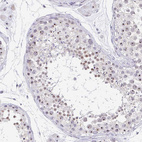

Immunohistochemical staining of human skin shows strong positivity in nucleoli in squamous epithelial cells.